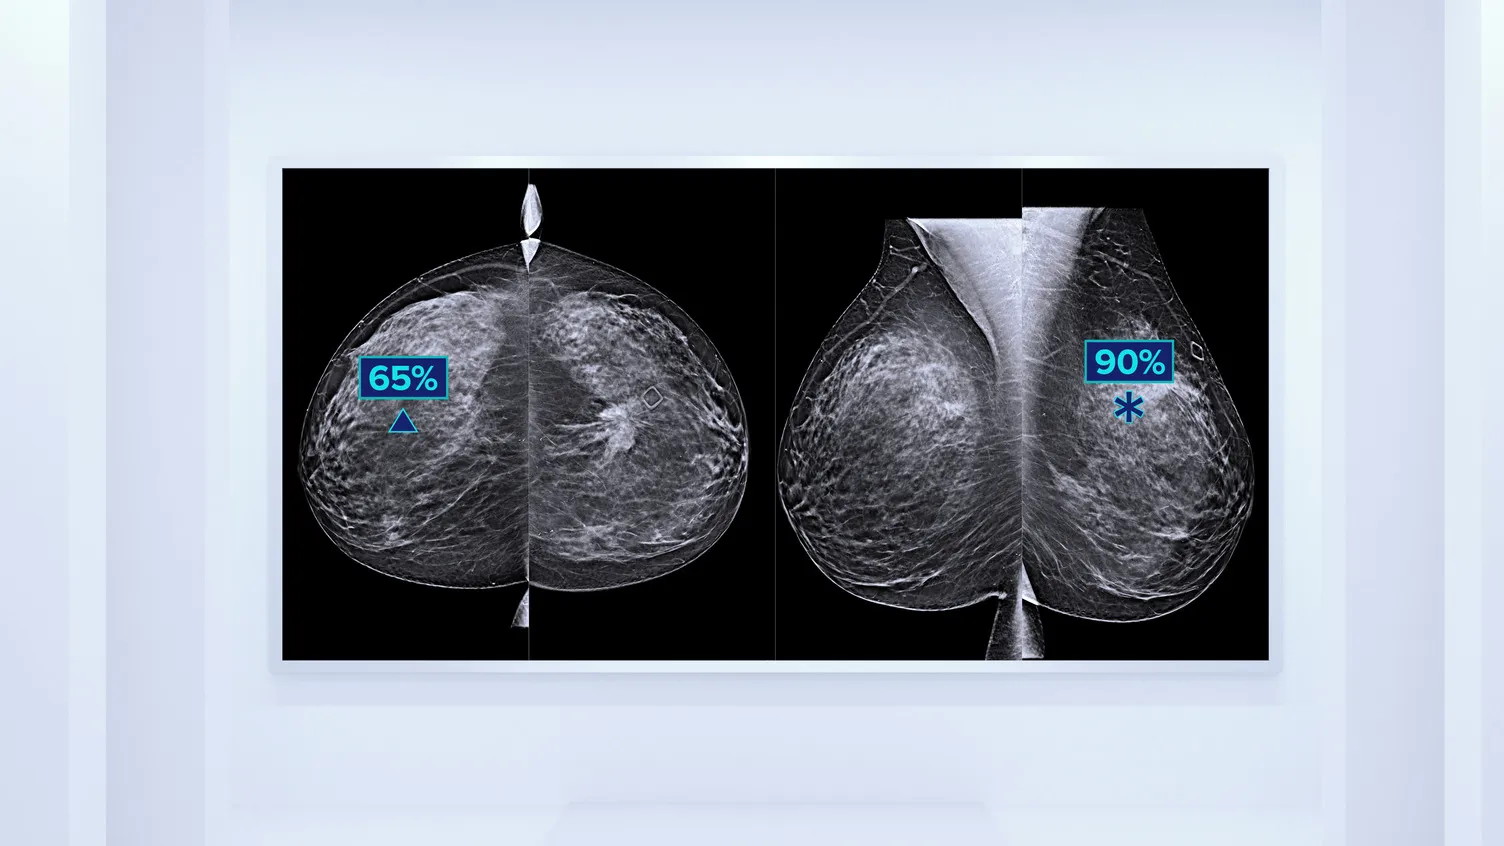

Reveal fine details with fast and high resolution 3D Mammography™ exam5 using our advanced detector and innovative 3D™ imaging technologies. These help to detect more invasive cancers with confidence6 With the integration of additional AI-powered solutions, this is a smart platform supporting breast cancer detection, workflow optimisation and risk assessment.

Clarity HD™ High Resolution Tomosynthesis

Producing high-resolution tomosynthesis images normally means slower read times. However, combining Clarity HD high-resolution 3D imaging with Genius AI Detection technology and 3DQuorum allows you to unleash fast and high resolution 3D images,5 accelerating screening and analysis.

Quantra™ Technology

Higher breast density is known to increase a woman’s risk for breast cancer.10,11 The need for accurate, unbiased analysis is therefore critical. Powered by machine learning, Quantra software analyses the breast tissue texture and pattern in both 2D and tomosynthesis images and categorises the breasts into four composition risk categories.12